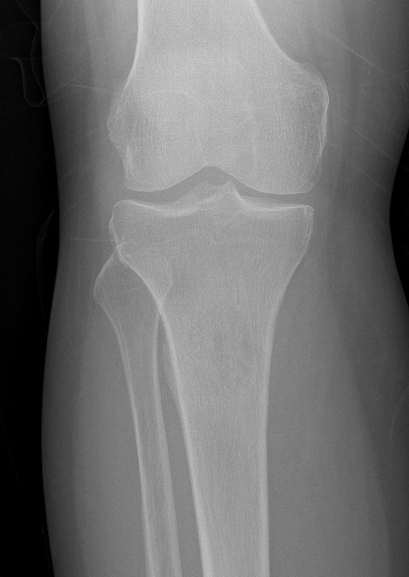

Tibia

Greenbaum et al Am J Orthop 2017

- 43 tibial metastasis

- proximal tibia most common

- variety of treatements

- plate / nail / arthroplasty